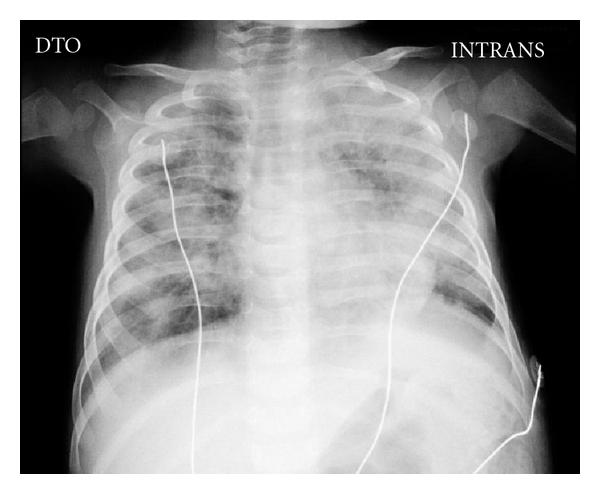

成功治疗一名重症联合免疫缺陷儿童的播散性卡介苗病

Successful Handling of Disseminated BCG Disease in a Child with Severe Combined Immunodeficiency.

In high-burden countries, Mycobacterium bovis Bacillus Calmette-Guérin (BCG) vaccine is administered in newborn to prevent severe Mycobacterium tuberculosis infection. Because life-threatening disseminated BCG disease may occur in children with primary immunodeficiency, vaccination strategy against tuberculosis should be redefined in non-high-burden countries. We report the case of a patient with X-linked severe combined immunodeficiency (SCID) who developed disseminated BCG disease, highlighting the specific strategies adopted.

在高负担国家,新生儿会接种卡介苗(BCG)以预防严重的结核分枝杆菌感染。由于原发性免疫缺陷儿童可能发生危及生命的播散性卡介苗病,因此在非高负担国家应重新定义结核病疫苗接种策略。我们报告了1例患有X连锁重症联合免疫缺陷(SCID)并发生播散性卡介苗病的患者病例,并着重介绍了所采取的具体策略。